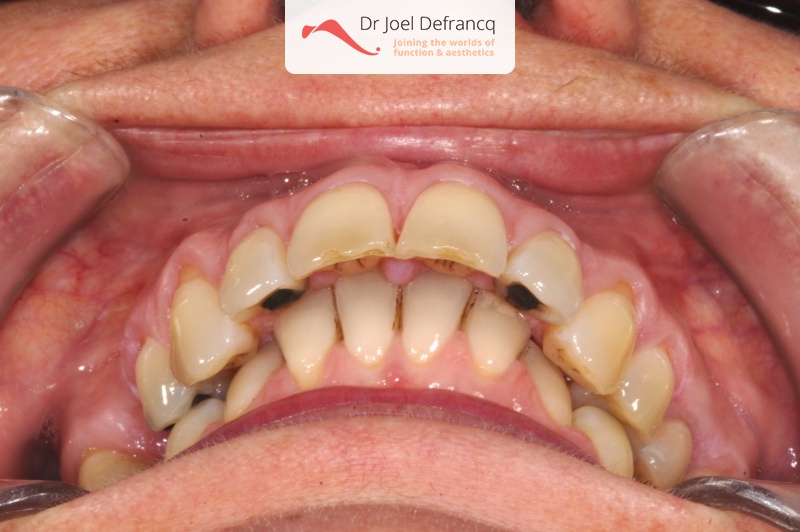

Paola: Diepe beet, overbeet

- Te kleine onderkaak (Overbeet)

- Diepe beet, vierkant gezicht

- Klasse II divisie 1

- Diepe beet